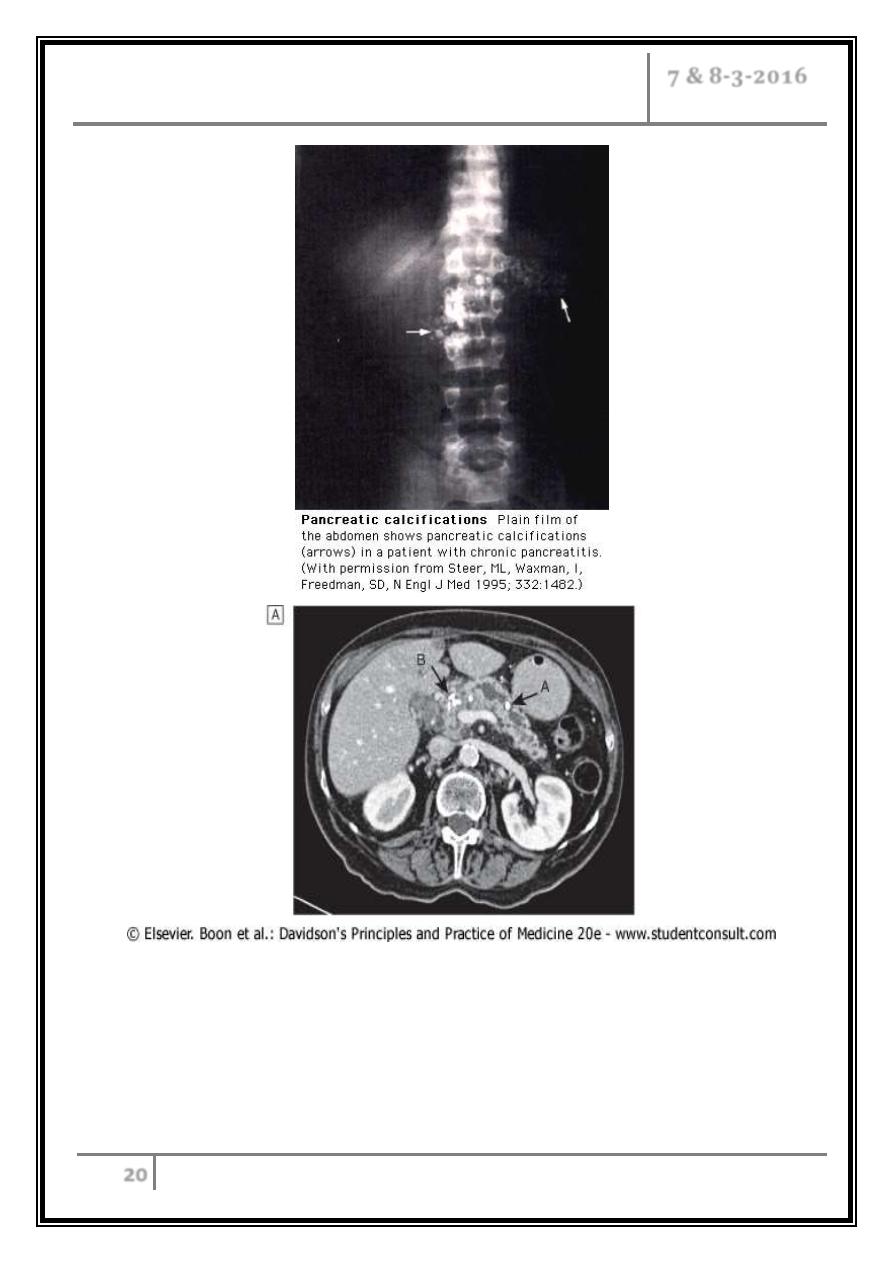

Tests to establish the diagnosis

- CT (may show atrophy, calcification or ductal dilatation).

- Abdominal X-ray (may show calcification).

Imaging in chronic pancreatitis. CT scan showing a grossly dilated and

irregular duct with a calcified stone (arrow A). Note the calcification in

the head of the gland (arrow B). MRCP of the same patient showing

marked ductal dilatation with abnormal dilated side branches (arrows A).

A small cyst is also present (arrow B).